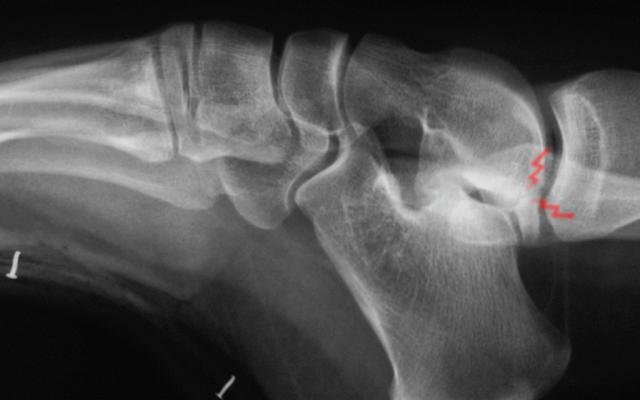

Osteochondral lesion in a patient with sequela of club foot